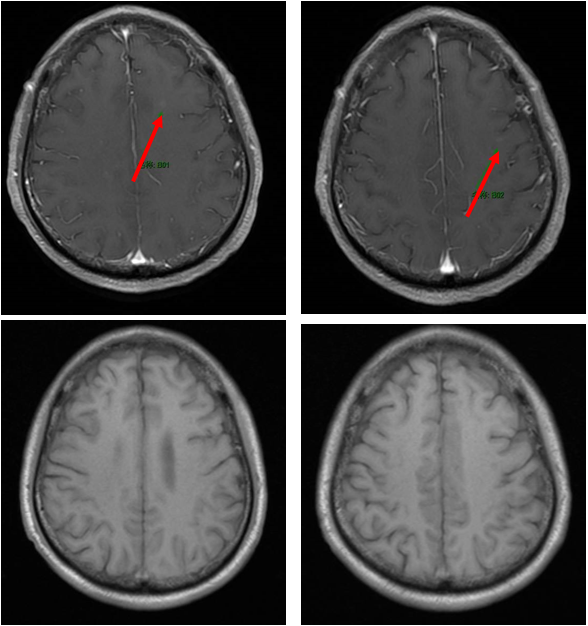

免疫联合化疗(2022年12月):紫杉醇+卡铂+PD-1抑制剂+贝伐珠单抗,共6周期。治疗后积液显著吸收,脑转移灶缩小。

维持治疗及随访(2023年6月至今):紫杉醇+PD-1抑制剂+贝伐珠单抗维持治疗。2025年6月MRD检测发现SMARCA4突变低丰度阳性,提示可能复发,需进一步评估。

新加坡国家癌症中心Kevin Lee Min Chua教授:在分析患者治疗情况时,我们发现其接受的系统治疗虽全面,但疾病控制效果短暂,每6个月随访便显示病情进展。同时,患者对紫杉醇+PD-1抑制剂+贝伐珠单抗维持治疗缓解不佳,这促使我们思考后续治疗策略。MRD检测揭示复发风险,却未明确复发位置。此时,借助PET-CT或脑部MRI检查,或许能定位潜在复发病灶。

上海交通大学附属胸科医院艾星浩教授:如果MRD从阴性转为阳性,这是重要的监测信号,但治疗方案的调整不能仅凭此一项指标。即只有当患者出现明确的疾病进展,特别是影像学上出现显著变化时,才考虑调整治疗方案。这样的判断标准能帮助避免因检测误差或早期波动而做出过激的治疗方案调整,确保治疗决策更加理性合理。

上海交通大学附属胸科医院陆舜教授:MRD虽具有一定预后价值,但目前尚缺乏足够证据支持其作为预测性生物标志物或用于临床终点评估,且在中国尚未有MRD检测获得NMPA批准。不过,若患者已接受MRD检测且结果由阴转阳,我会密切监测,直到影像检查发现复发、进展或新发病灶,再调整治疗方案。对于携带EGFR 19外显子缺失突变的患者,由于此突变对EGFR-TKI治疗的敏感性尚未明确,该患者对TKI治疗无缓解,治疗思路需跳出标准EGFR-TKI路径。对于术后局部复发的患者,通常会优先推荐放疗,但该患者拒绝这一局部治疗方案,错失最佳干预时机。鉴于患者表现为PD-1高表达,同时又不具备典型EGFR敏感突变,若患者拒绝同步放化疗,可考虑免疫治疗联合化疗作为替代方案,这已成为PD-1高表达患者的常用标准治疗策略之一。若出现寡进展,可评估是否可行局部治疗;若为系统性进展,则需考虑更换全身治疗方案,如ADC药物或双特异性抗体等。